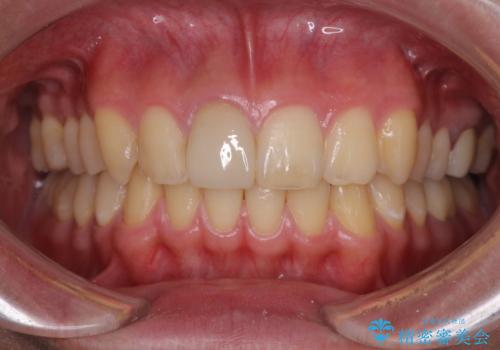

- 治療中の前歯と口腔内にある銀歯が気になるとのことで来院された患者様です。

土台に含まれている金属も含め、口腔内の金属は全て除去し、根管治療が必要な歯は根管治療を行い、オールセラミッククラウンやセラミックインレーにて治療することとしました。

途中来院されない時期があったため、初診から終了まで期間がかかりましたが、根管治療を行った歯の根尖病変はいずれも改善を確認することができました。

口腔内の金属が全てなくなり、患者様には大変満足していただきました。